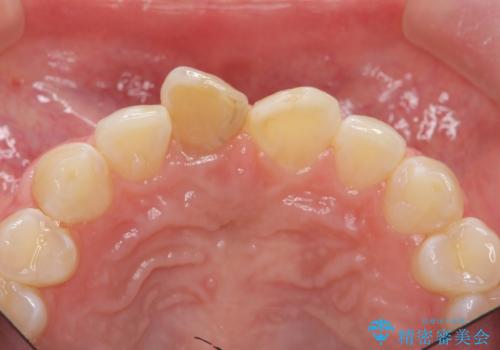

前歯をきれいにしたい ジルコニアクラウンによる審美治療

ジルコニアクラウンによる審美性の改善を計画します。

今回失活歯であったため捻転を取り反対側の前歯に揃えて補綴を行うことができました。